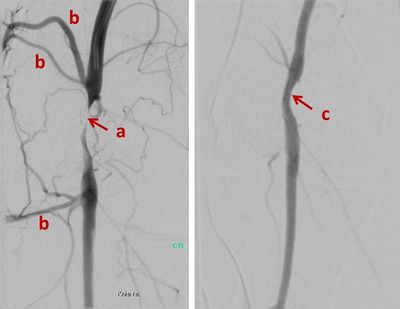

Interventional procedures using ionising radiation have revolutionised medicine in the past few decades for therapy and palliation, resulting in more patients being offered treatments that would not have been possible before with more invasive open surgery. The vast majority of interventional procedures are performed as “minimal invasive percutaneous therapies”.

As technology continues to advance, interventional procedures become more complex and some may take several hours to complete. New technologies with smaller catheters, guidewires, stents, filters and many other devices also present new challenges for radiological protection, such as aortic stent grafts, cardiac valve replacement, prostate embolisation, thrombus aspiration after stroke or selective internal radiation therapy (SIRT).

Physicians, assisted by nurses and radiographers, perform X-ray guided interventions as an alternative to conventional surgery. Most of these interventions are less invasive, the recovery periods are shorter, and for many types of interventions the complication rate is lower. In addition, some patients who may not tolerate anaesthesia and conventional surgery, as well as lesions that were not previously accessible, can now be treated by less-invasive image-guided interventions. In addition, interventional procedures offer new therapies where options of other medical specialties do not exist, such as embolization of liver tumours with chemical drugs or radioisotopes (SIRT).

The number of image guided interventions is increasing continuously in both developed and developing countries. New types of interventions are also of increased complexity, require extensive use of X-ray imaging, and raise new issues of occupational and patient protection.

Interventions are usually guided by fluoroscopy. Radiographic cine series or stored images from fluoroscopy are taken to document the outcome of diagnosis or treatment. Interventions can also be guided by computed tomography (CT) imaging, with images taken while the interventionalist steps behind a shield or out of the room, or by CT fluoroscopy, in which the interventionalist stays at the patient for obtaining images during device manipulation.